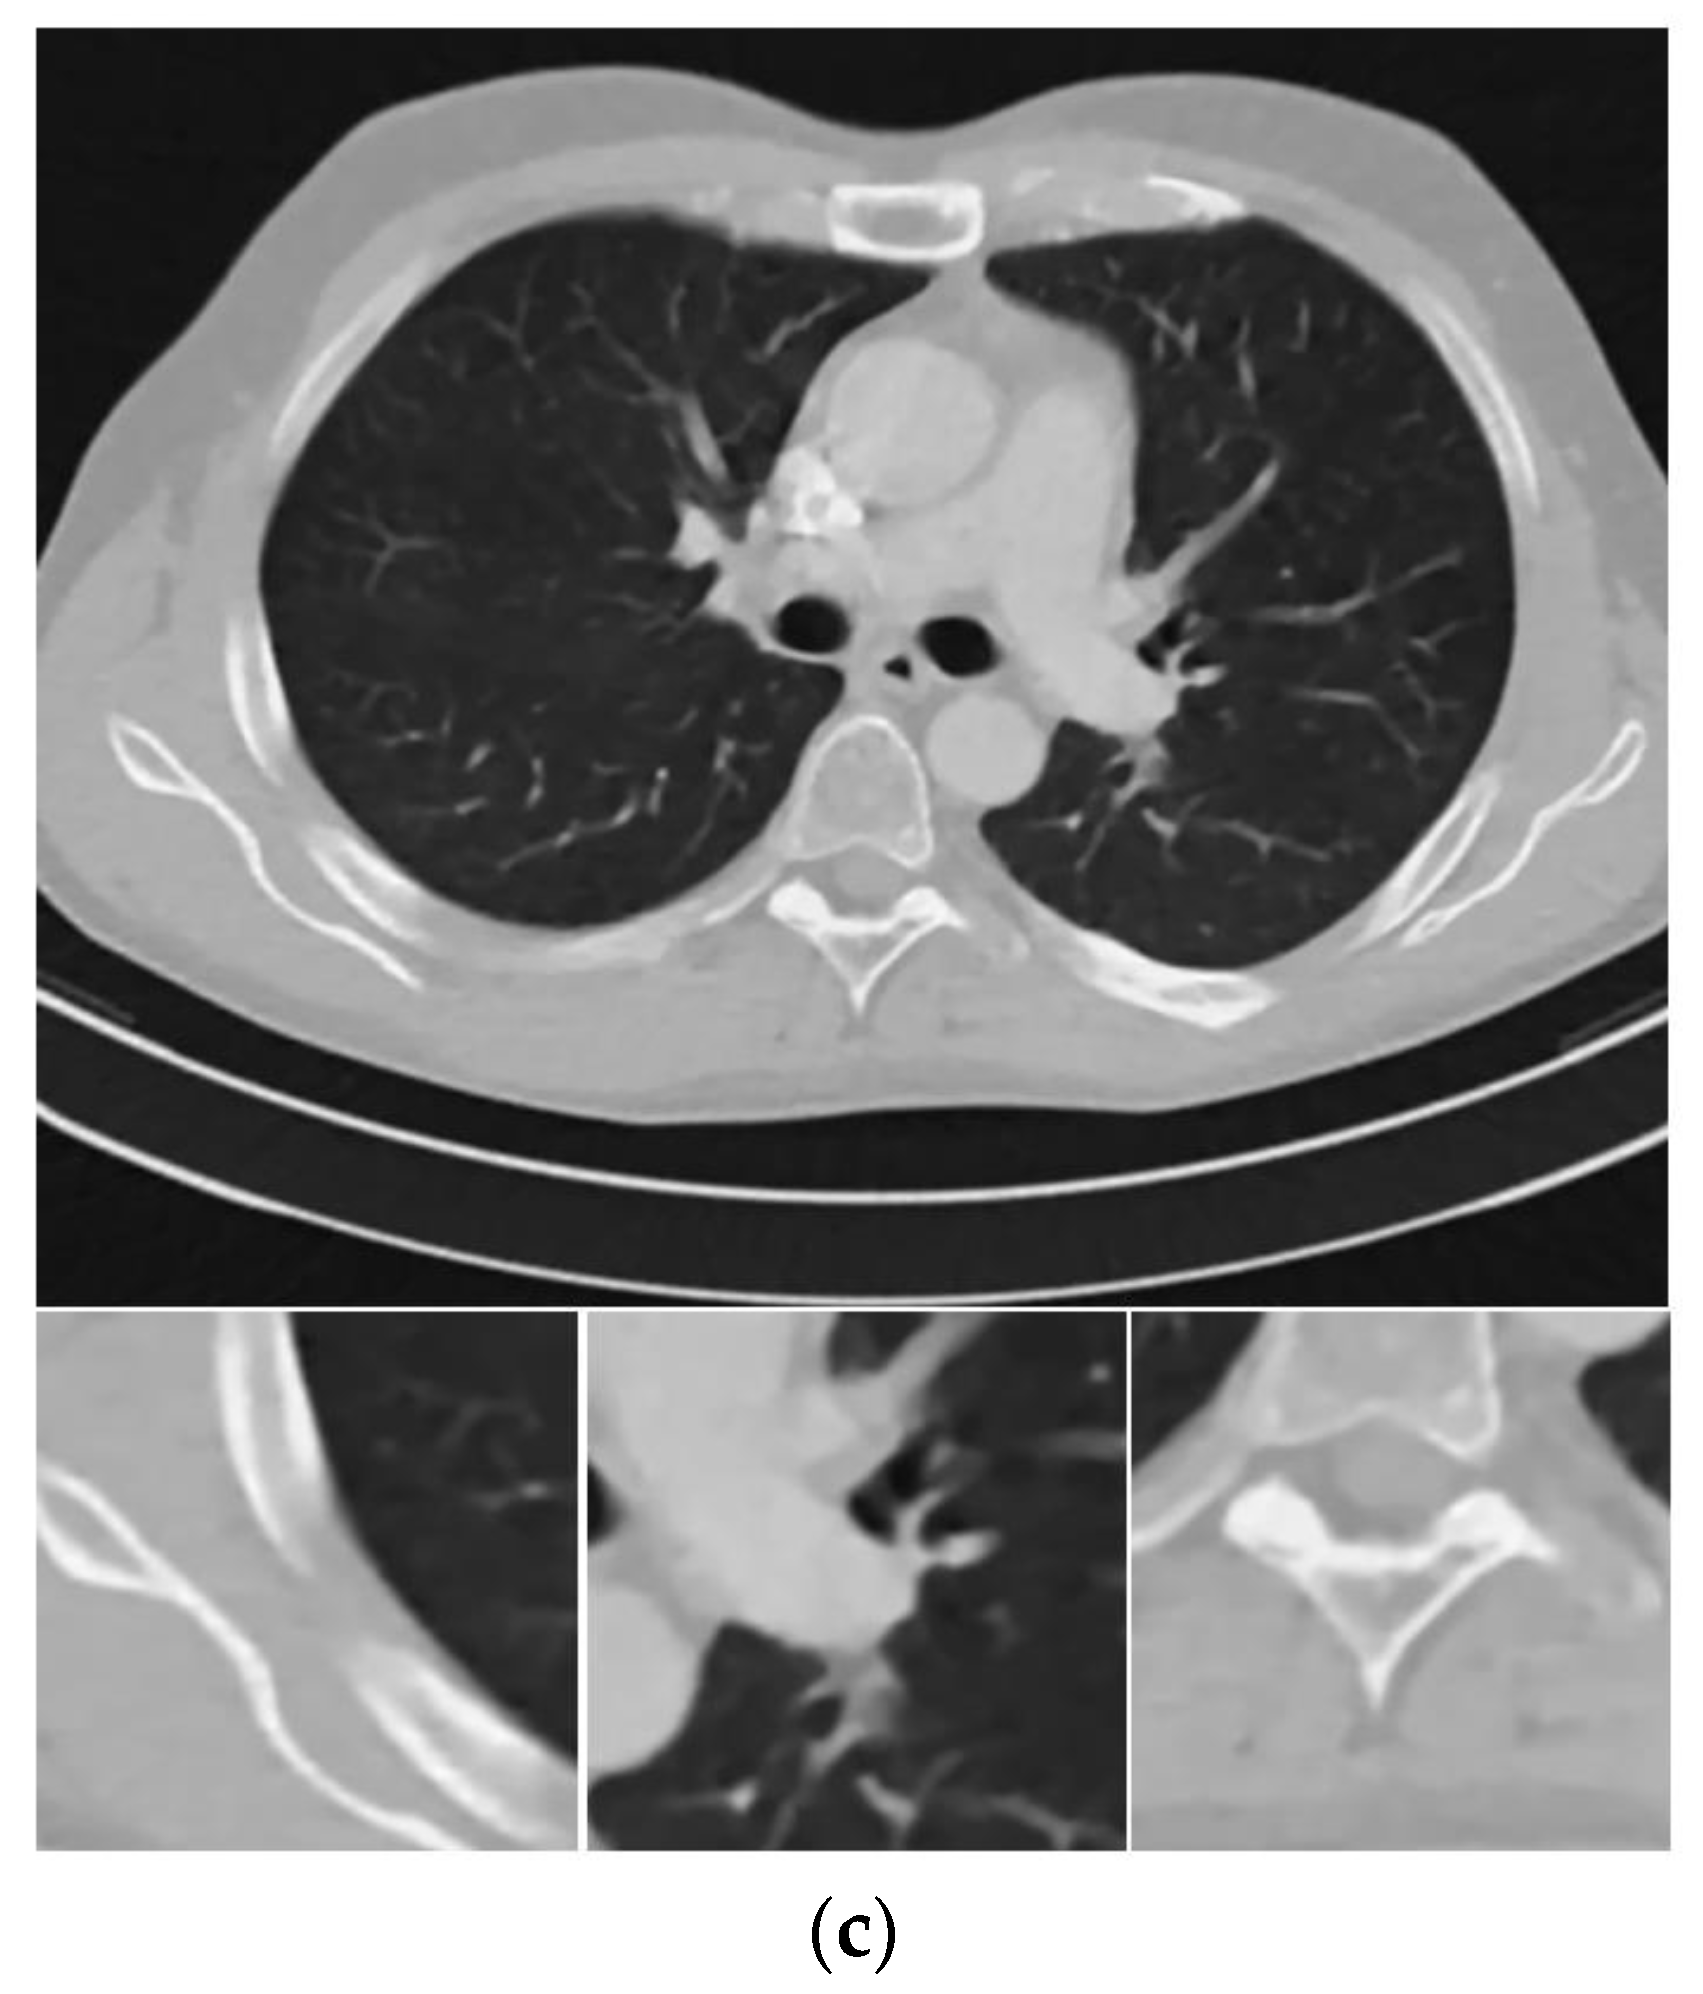

Figure 4 shows the reconstructed images from noisy projections with incident photon numbers 5 × 104 by the FBP, SIR-TV, and SIR- STV1 methods. In the proposed SIR-STV1 method, σ is set to 0.5, L K is set to be 3, and λ is set to 2 × 10 6 . It can be seen that SIR-TV and SIR-STV1 can remove noise effectively and the SIR-STV1 method performs better in eliminating blocky effect than SIR-TV.

Figure 4. Thorax CT images reconstructed by (a) FBP, (b) SIR-TV, and (c) SIR-STV1 methods from noisy projections with 5 × 104 incident photon number. The display window is [−1000, 667] HU.

Sensors 20 01647 g004aSensors 20 01647 g004b